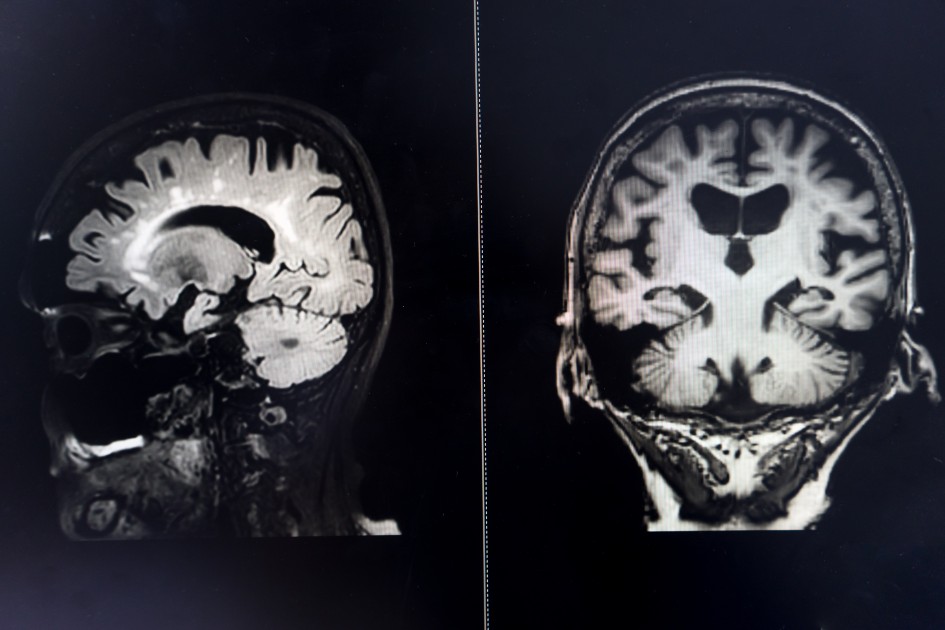

brain MRI for education Dementia Mix type stroke VaD

Only a neurologist can diagnose dementia using these tests, each of which is neither necessary nor sufficient. On the other hand, other tests such as MRI brain imaging or genetic mutation testing may support or refute the diagnosis. On the other hand, each of the cognitive abilities assessed by these tests can be diminished in the elderly person without dementia.

Diagnosis is clinical and now involves high-performance diagnostic tests such as a full neuropsychological assessment of cognitive functions, imaging tests such as MRI and glucose PET that highlight areas of the brain that are suffering, and lumbar puncture that is capable of showing the biological signs of the disease, i.e. the presence of abnormal deposits of amyloid and tau proteins.